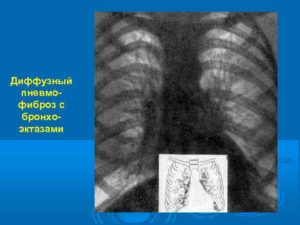

Локальная форма — при этой форме ткань легких теряет свои функции и замещается на соединительную ткань единственный участок органа. Диффузный пневмофиброз — это одна из тяжелых форм болезни, при которой поражается ткань целого органа, а иногда и обоих легких.

Объем пораженной поверхности сильно уменьшается за счет уплотнения и деформации тканей, вентиляция нарушается.

В медицинской практике встречается пневмофиброз локального и диффузного вида. Заболевание локального типа характеризуется уплотнением отдельного фрагмента легкого. Явных нарушений газообменных процессов не наблюдается. Диффузный пневмофиброз легких приводит к тому, что они утрачивают первоначальную структуру и форму, увеличивается их плотность, нарушается вентиляция.

- Диффузный пневмофиброз легких – это наиболее опасная форма заболевания, характеризующаяся множественными поражениями или изменениями всей ткани легкого. Для диффузной формы патологии характерно стремительное прогрессирование, развитие выраженной дыхательной недостаточности. В большинстве случаев состоянию сопутствует развитие плеврофиброза. Плевропневмофиброз легких – это поражение плевры, замещение ее на фиброзную ткань;